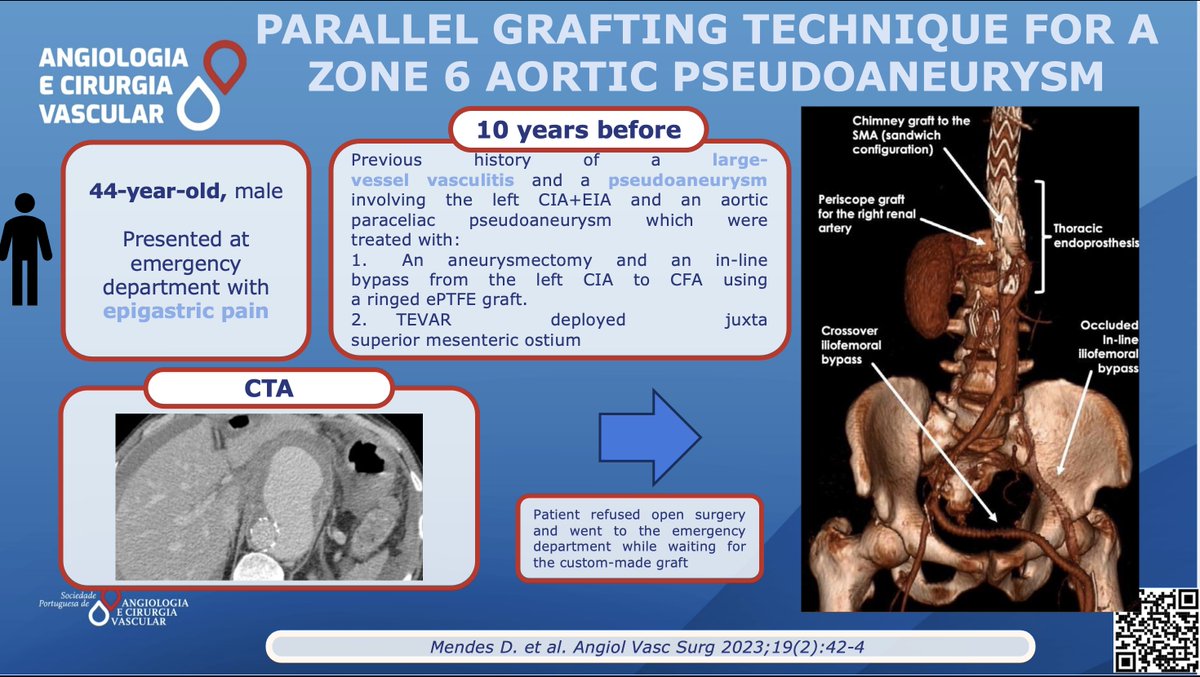

Mendes D. et al performed a parallel graft thechnique for a zone 6 aortic pseudoaneurysm. You can read more here lnkd.in/dPwgs6N8 #SPACV #Vascularsurgery ESVS European Vascular Surgeons in Training (EVST) Society for Vascular Surgery Vascular News